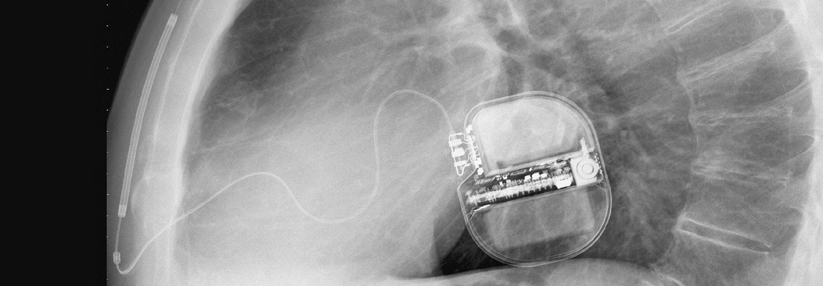

Implantierbare Kardioverter-Defibrillatoren: Transvenös oder subkutan?

Subkutan implantierbare Kardioverter-Defibrillatoren verursachen periinterventionell weniger Komplikationen als transvenös eingesetzte. Ob sie genauso zuverlässig arbeiten, wurde jetzt untersucht.

Für mehrere Dekaden gab es nur die Möglichkeit, implantierbare Kardioverter-Defibrillatoren (ICD) zur Prävention des plötzlichen Herztods auf transvenösem Weg intrathorakal zu platzieren. Damit gehen erhebliche akute Komplikationen wie Pneumothorax oder Herzperforation einher. Auf lange Sicht gehören Sonden-Endokarditiden und -Dislokationen zu den möglichen Zwischenfällen. Um solche Probleme zu vermeiden, wurden subkutan implantierbare ICD entwickelt.